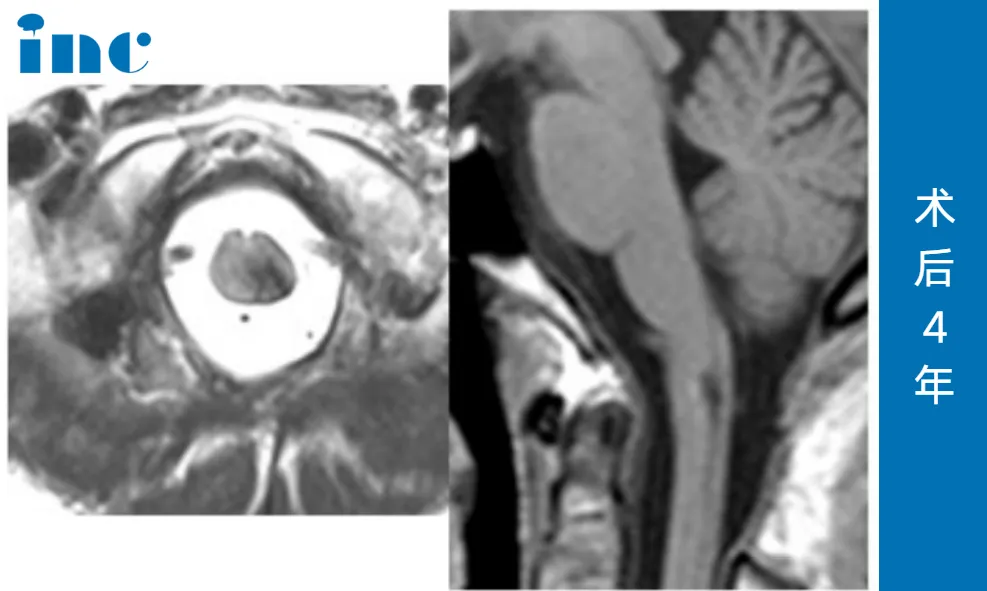

术后两年,王女士再次联系巴特朗菲教授复查,教授仔细对比历次影像后给出评价:"结合既往出血史,当前病灶无复发迹象,稳定性良好。"

术后四年,在今年7月的最新复查,更是给了王女士一颗“定心丸”——海绵状血管瘤已经被完全切除,术区仅存手术相关的良性瘢痕及含铁血黄素沉积(均为此类术后正常表现),无任何神经功能缺损。